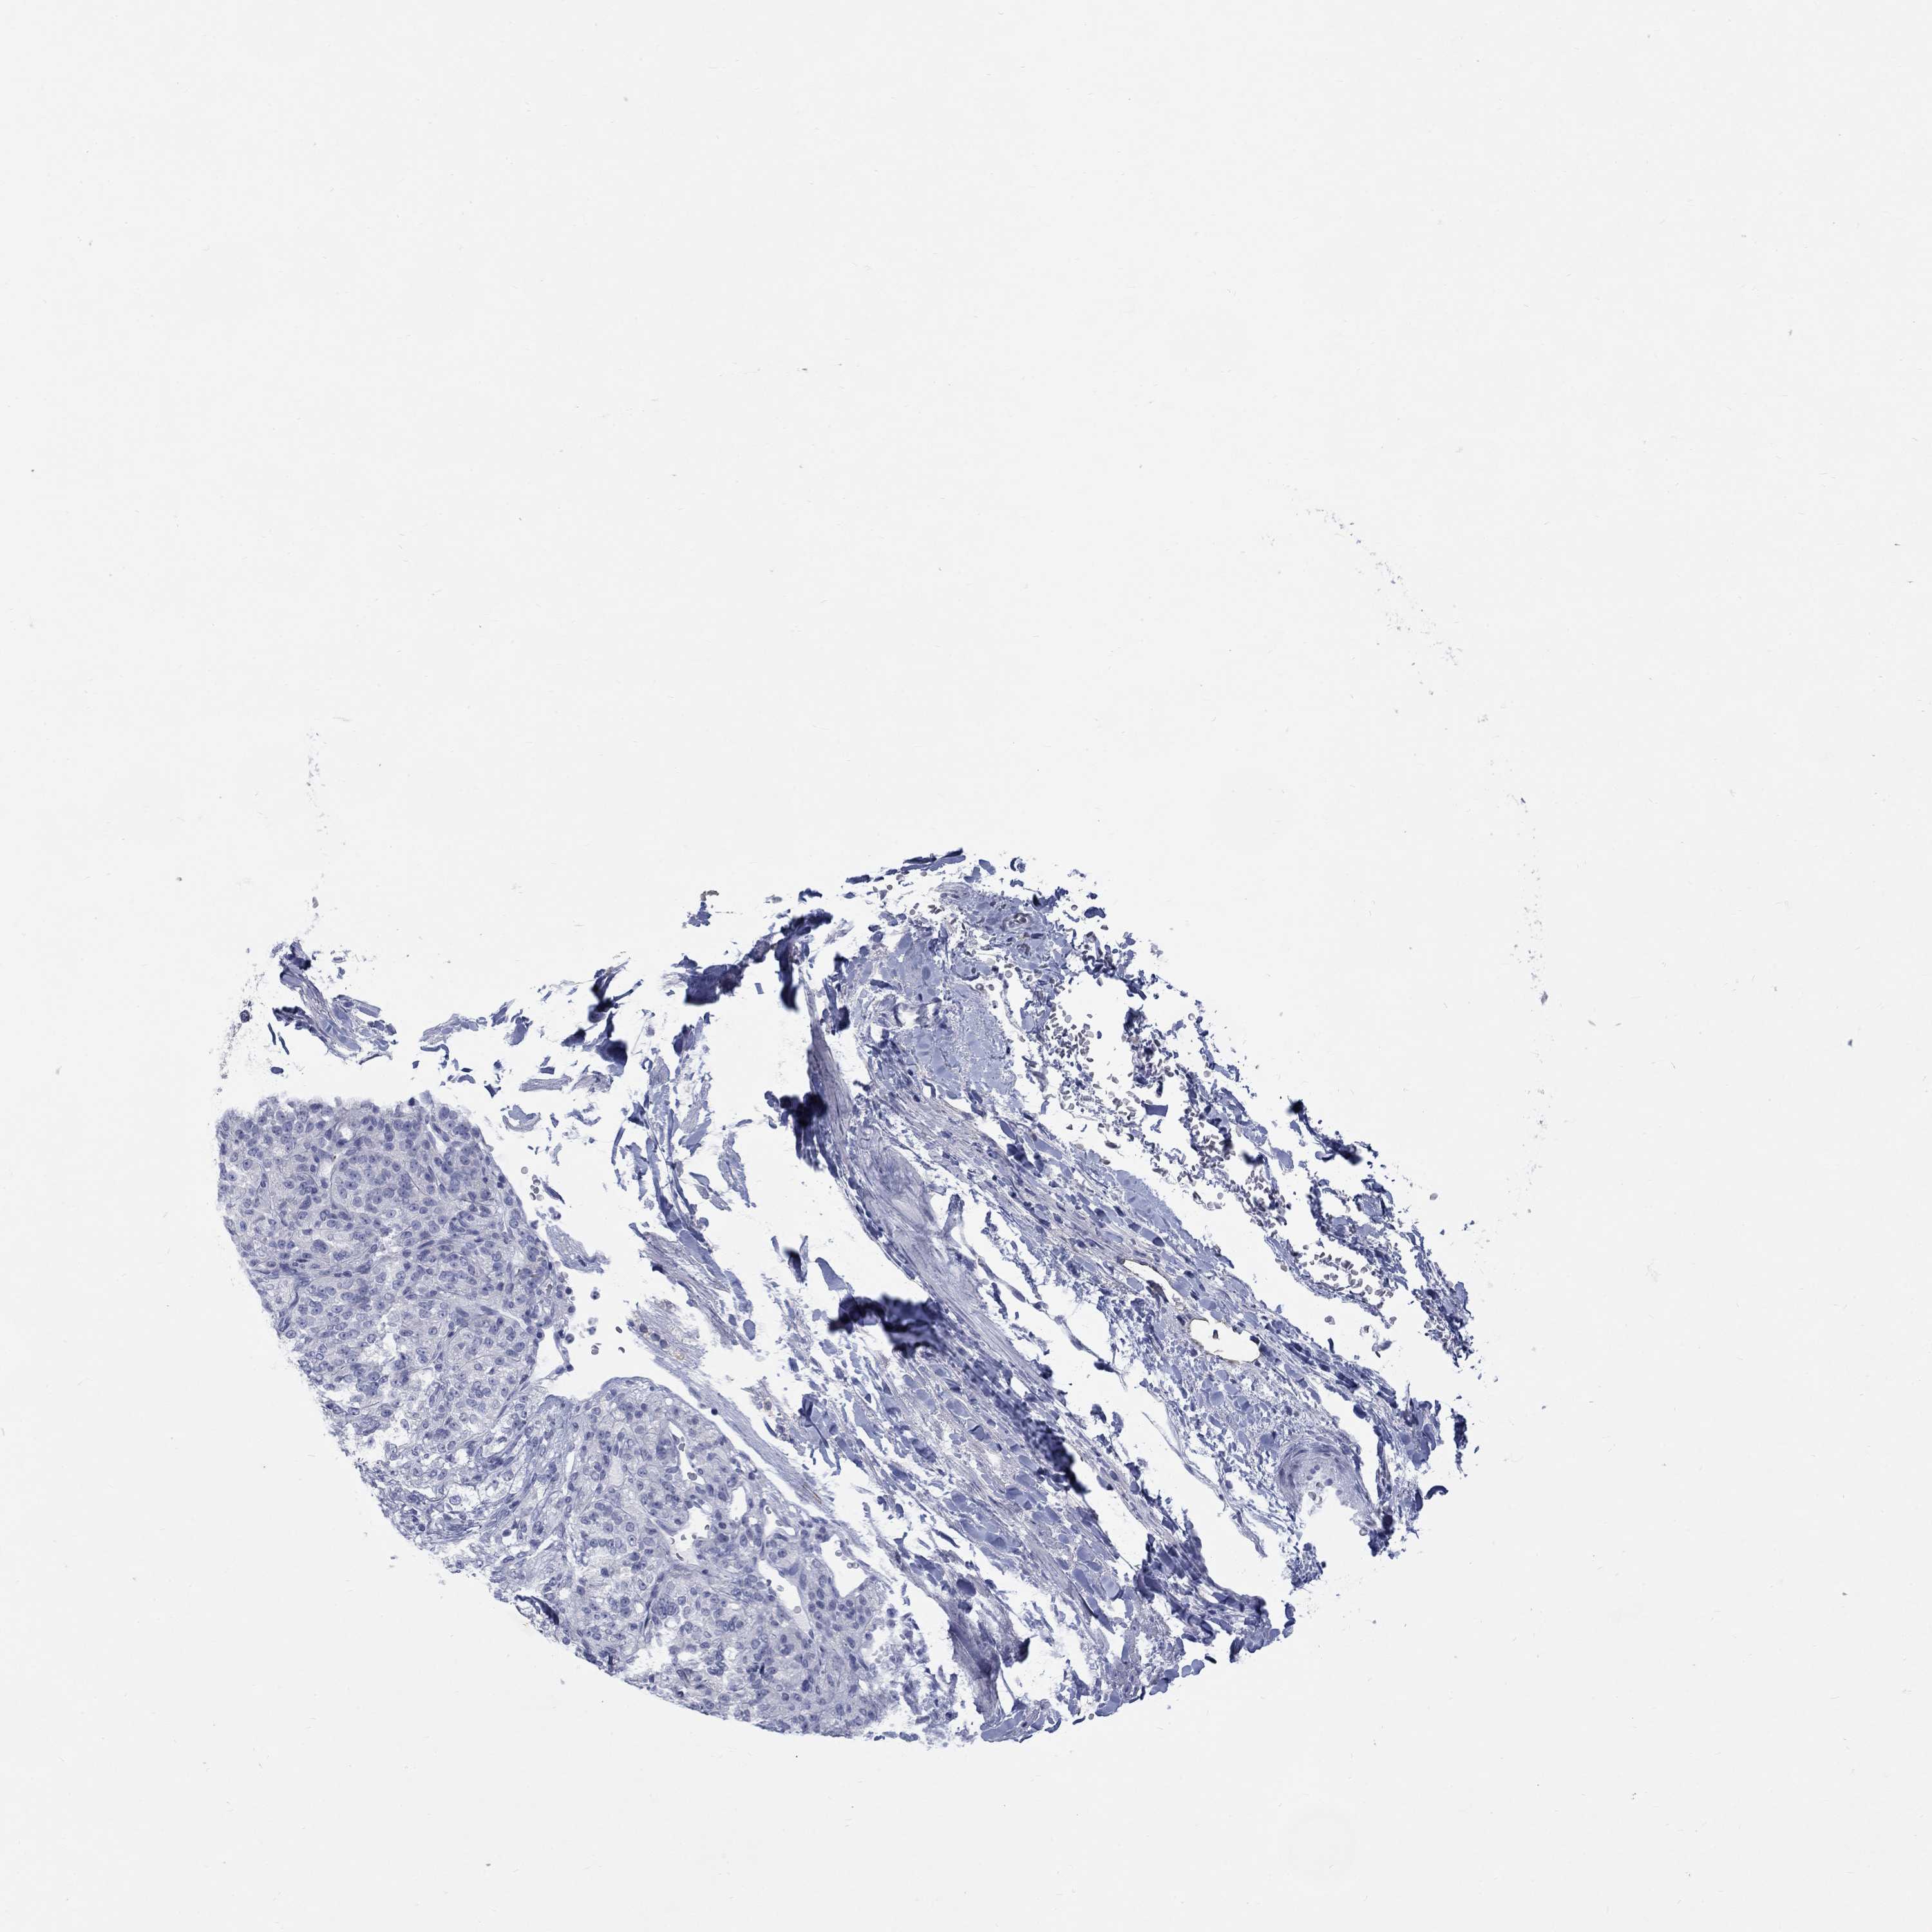

KIDNEY RENAL CLEAR CELL CARCINOMA (VALIDATION) - Interactive survival scatter ploti

The Survival Scatter plot shows the clinical status (i.e. dead or alive) for all individuals in the patient cohort, based on the same data that underlies the corresponding Kaplan-Meier plots. Patients that are alive at last time for follow-up are shown in blue and patients who have died during the study are shown in red.

The x-axis shows the expression levels (FPKM) of the investigated gene in the tumor tissue at the time of diagnosis. The y-axis shows the follow-up time after diagnosis (years). Both axes are complimented with kernel density curves demonstrating the data density over the axes. The top density plot shows the expression levels (FPKM) distribution among dead (red) and alive patients (blue). The right density plot shows the data density of the survived years of dead patients with high and low expression levels respectively, stratified using the cutoff indicated by the vertical dashed line through the Survival Scatter plot. This cutoff is automatically defined based on the FPKM cutoff that minimizes the p-score. The cutoff can be changed by dragging the vertical line or by entering a cutoff value in the square labeled "Current cut-off".

Under the Survival Scatter plot the p-score landscape (black curve; left axis) is shown together with dead median separation (red curve; right axis). Dead median separation is the difference in median mRNA expression between patients who have died with high and low expression, respectively. It is calculated as follows: median FPKM expression of dead patients with high expression - median FPKM expression of dead patients with low expression. This is intended to aid the user in visually exploring custom cutoffs and the associated p-scores and dead median separation.

Individual patient data is displayed and can be filtered by clicking on one or more of the category buttons on the top of the page. Categories describing expression level and patient information include: high, low, alive, dead, female, male and tumor stages. The scale of the x-axis can be toggled between linear and log-scale by clicking on the "x log" button. Mouse-over function shows TCGA ID, patient information and mRNA expression (FPKM) for each patient.

& Survival analysisi

Kaplan-Meier plots summarize results from analysis of correlation between mRNA expression level and patient survival. Patients were divided based on level of expression into one of the two groups "low" (under cut off) or "high" (over cut off). X-axis shows time for survival (years) and y-axis shows the probability of survival, where 1.0 corresponds to 100 percent.

RFTN2 is validated prognostic, high expression is favorable in Kidney Renal Clear Cell Carcinoma (validation)

Best expression cut offi

Based on the FPKM value of each gene, patients were classified into two groups and association between prognosis (survival) and gene expression (FPKM) was examined. The best expression cut-off refers the FPKM value that yields maximal difference with regard to survival between the two groups at the lowest log-rank P-value. Best expression cut-off was selected based on survival analysis .

When clicking on this number, the vertical dashed line indicating cut-off, the interactive survival plot, and the Kaplan-Meier curve will be adjusted to show results based on the best expression cut-off.

: 3.05

Average pTPM 3.8

Number of samples 100